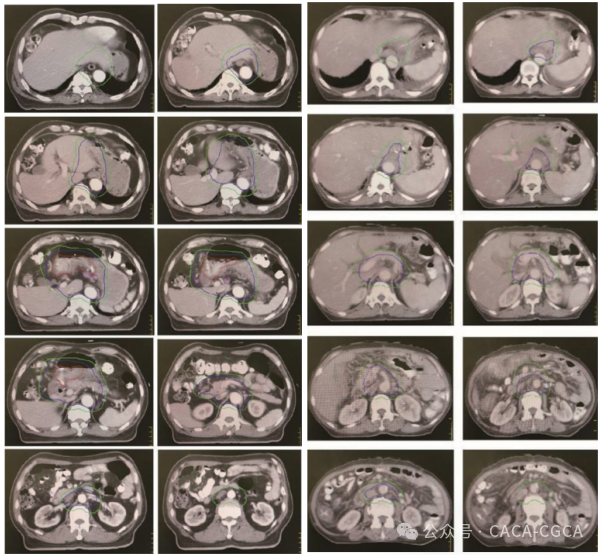

(六)新增术前、术后放疗靶区勾画示意图

胃癌术前(左)术后(右)放疗靶区勾画示意图

注:红色:GTV、粉色:GTVnd、蓝色:CTV、绿色:PTV